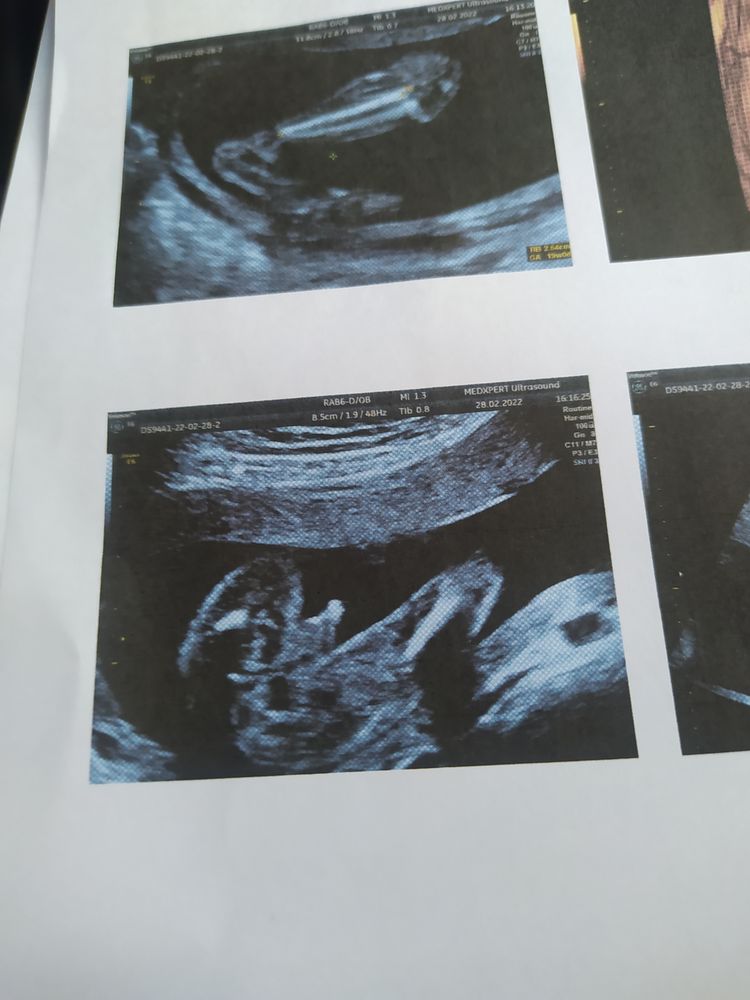

А какой срок? Если 20 недель ,то так не смотрят, а между ножек. Скорее всего мальчик, но если на этом фото срок меньше 15 - Ти недель, то девочка

15.11.2021

Мечты сбываются , на этом узи 12 недель

Александра, тогда девочка